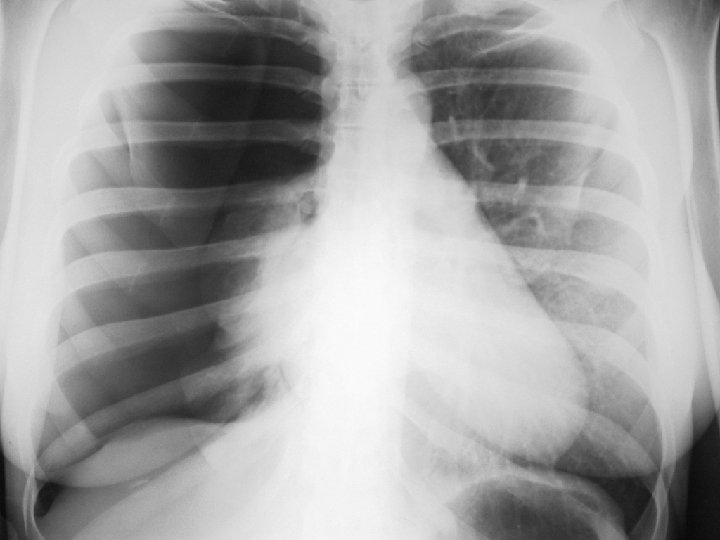

PNT spontanée du sujet jeune Le pneumothorax est lié à la rupture de bulles d’air sous -pleurales. CDD : douleur thoracique brutale spontanée ou lors d’un effort. Parfois dyspnée Examen : tympanisme hémithoracique. Recherche de signes de détresse respiratoire (polypnée, cyanose, sueur, tirage…) Radio : hyperclarté périphérique séparée du poumon par le « liséré capillaire » : image de la plèvre viscérale. La radio fait le diagnostic

DIAGNOSTIC CDD : Dyspnée, Douleur Autres signes en fonction de l’étiologie Examen : syndrome pleural : matité, abolition de la transmissions des vibrations vocales, abolition du murmure vésiculaire Radio : opacité dense, limitée par une ligne concave en haut et en dedans : la ligne de Damoiseau Bilan biologique : en fonction de l’étiologie